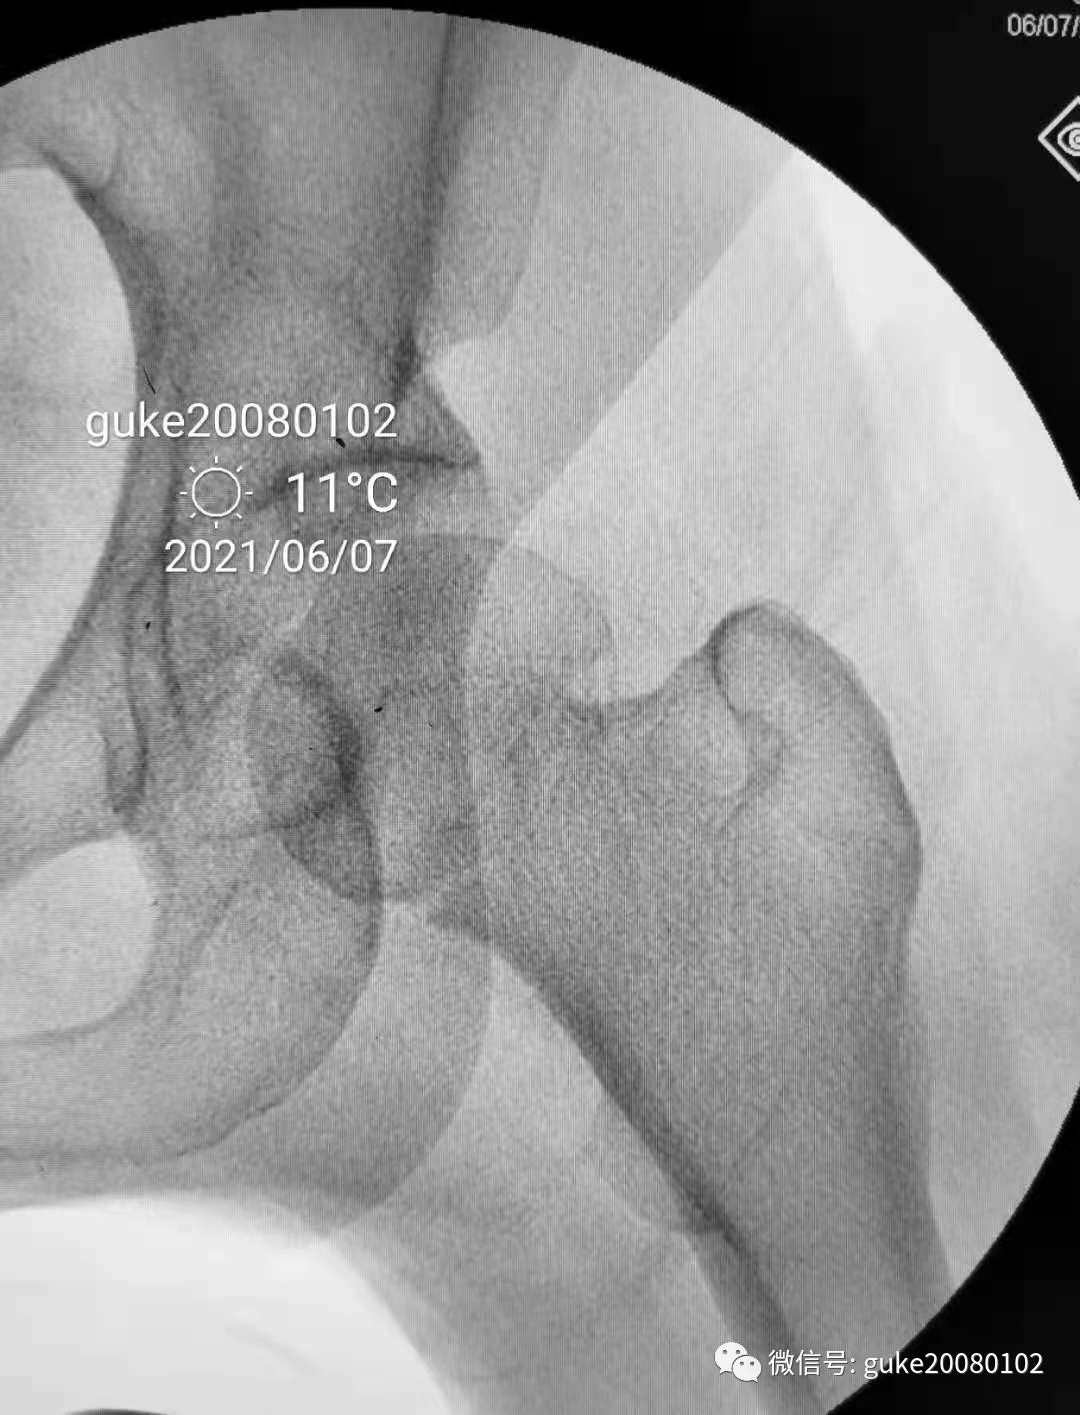

患者置于牵引床上,固定骨盆,尝试Ledbetter法复位,透视见复位不佳。骨折断端崁插,股骨头外翻。